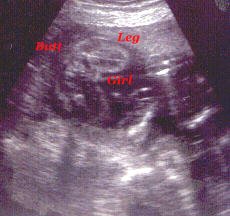

This is my hand up by my face.

Still up by my face.